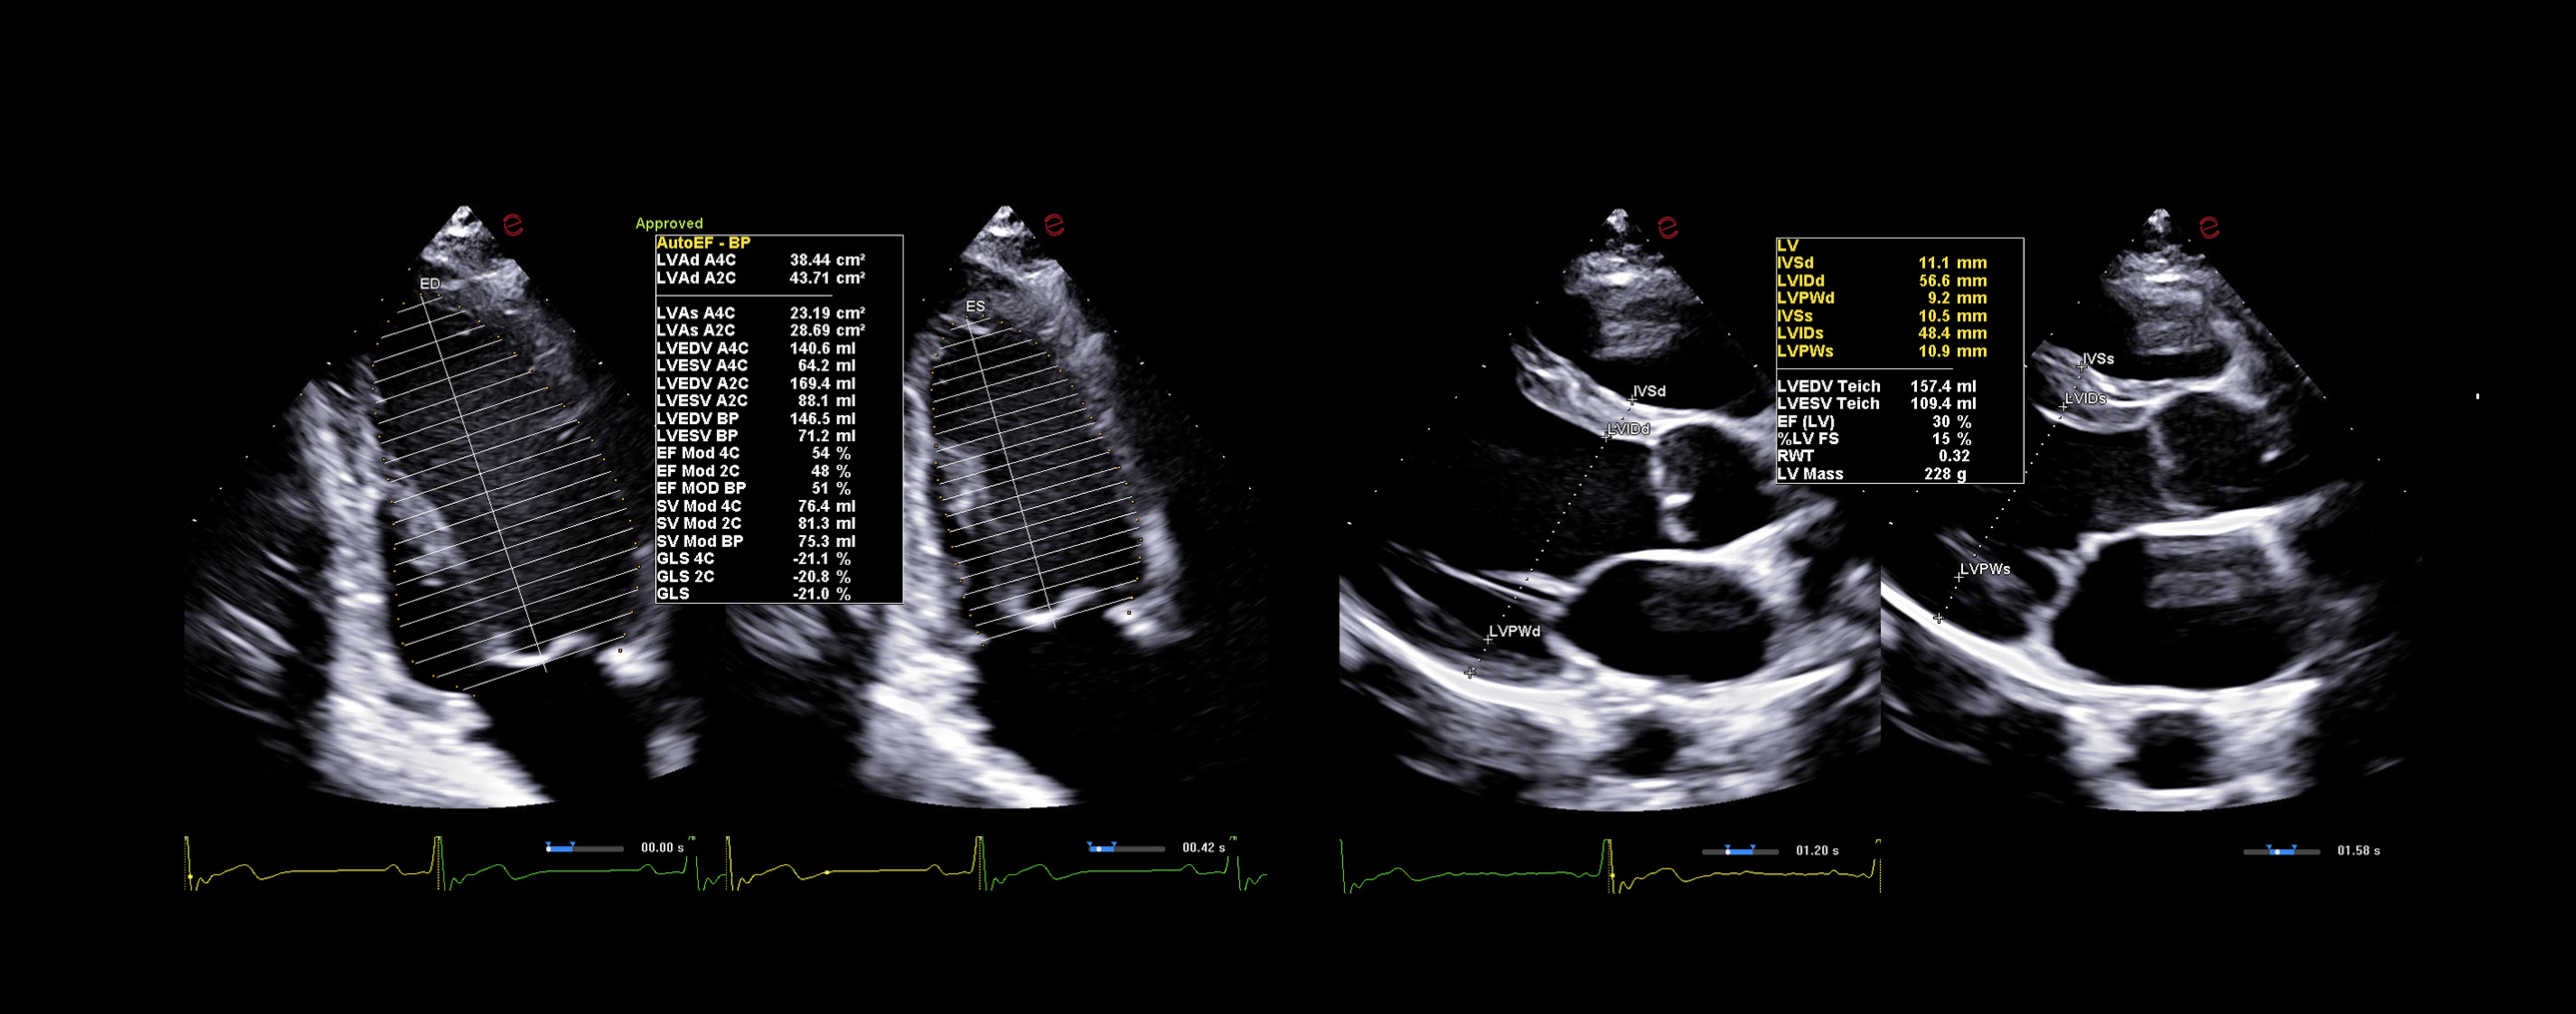

AI-based cardiac measurements for speed and consistency

Esaote’s AutoEF and AutoCM tools are designed to bring a step ahead in the device use experience. With advanced AI algorithms, AutoEF automatically recognizes apical views and traces endocardial borders offering a proposal of left ventricular volumes and ejection fraction in just seconds. AutoCM complements this by automatically suggesting ventricular wall thickness, internal diameters, and derived values such as LV mass and fractional shortening directly from parasternal views. Moreover, AutoCM assists cardiologists by automatically recommending a calculation of the E/A wave ratio of the mitral valve, providing crucial information on diastolic function.

Together, these tools help clinicians to obtain accurate, guideline-aligned measurements in a fast way, enhancing diagnostic reliability. AutoEF and AutoCM automate key functional and structural measurements—such as ejection fraction, LV volumes, wall thickness, and LV mass— making a smooth workflow, especially in high-throughput clinics.